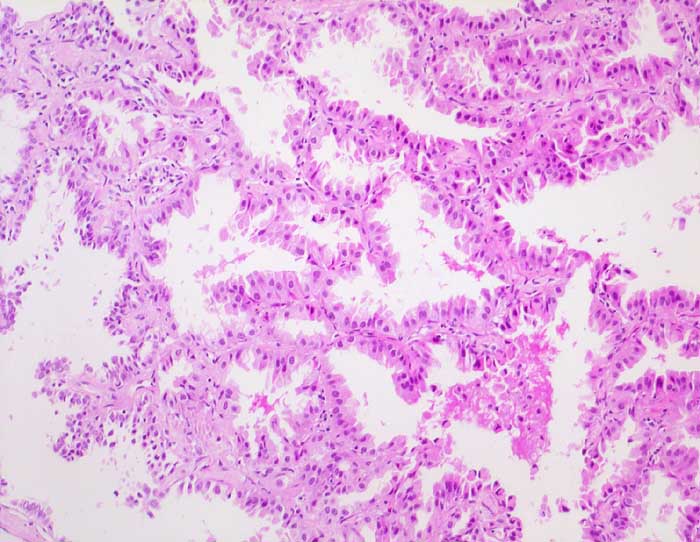

n/ Bronchioloalveoläres Karzinom der Lunge

Bronchioloalveoläres Karzinom der Lunge

Das Bronchioloalveoläre Karzinom stellt eine Variante des Adenokarzinoms dar. Die Tumorzellen wachsen per Definition auf dem intakten Alveolargerüst, ohne das Stroma zu infiltrieren. Nicht selten zeigen Ausläufer gewöhnlicher Adenokarzinome ein bronchioloalveoläres Wachstumsmuster. Bei diesen Tumoren handelt es sich jedoch nicht um echte bronchioloalveoläre Karzinome. Da eine Invasion zytologisch nicht ausgeschlossen werden kann, ist die zytologische Diagnose eines bronchioloalveolären Karzinoms nicht eindeutig möglich. Die Karzinomzellen schilfern in kleinen Gruppen oder dreidimensionalen Verbänden in die Alveolarlichtungen ab. Multiple kleine papilliforme Zellverbände, die mit Creolakörperchen verwechselt werden können, sind typisch. Im Sputum erscheinen die Tumorzellen kleiner als die der üblichen Adenokarzinome. Die Kerne liegen exzentrisch, sind rund und glatt begrenzt, das Chromatin ist blass. Kernkerben und Pseudoinklusionen sind möglich, Nukleolen sind unauffällig. Das reichlich vorhandene Zytoplasma färbt sich blass eosinophil bis blass zyanophil. Beim muzinösen Subtyp ist es unterschiedlich vakuolisiert. Aufgrund der geringen Kernatypien ist die Unterscheidung von einer Becherzellhyperplasie bisweilen schwierig. Pseudoepitheliale Verbände aktivierter Makrophagen und hyperplastische Alveolarzellen, wie sie bei Lungeninfarkten oder Lungenfibrosen vorkommen verschwinden im Gegensatz zum ähnlich aussehenden bronchioloalveolären Karzinom in wiederholten Sputumkontrollen.

Der erste Fall zeigt ein muzinöses, der zweite Fall ein nicht muzinöses bronchioloalveoläres Karzinom.